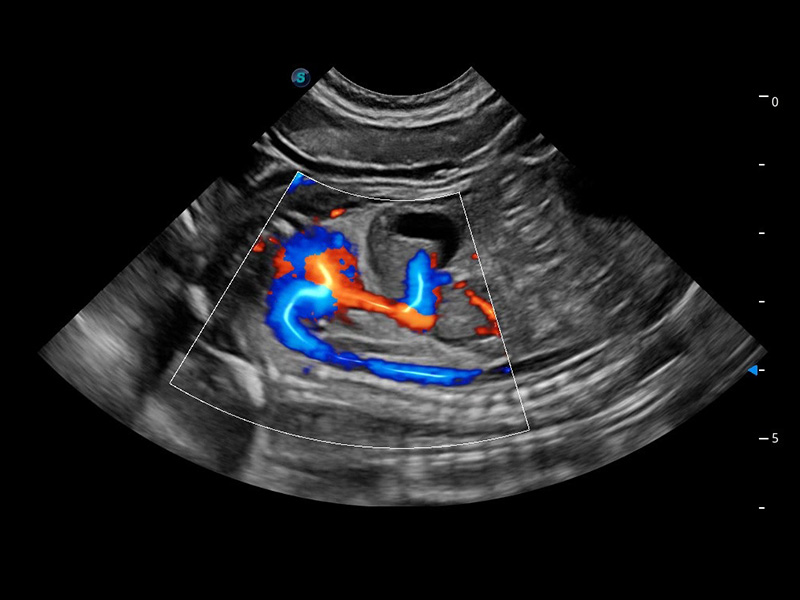

ProPet 60 作为一款高端台式动物超声设备,为动物医生的日常诊断提供了一系列贴合动物临床需求、解决临床实际问题的高级成像功能。凭借全系列高清探头,满足医生对腹部、心脏、生殖、浅表、肌骨等成像的所有需求,切实帮助您提升检查效率,提高诊断信心。

动物是人类最亲密的朋友和最值得信赖的伙伴。竞技宝(JJB)官方网站也一直致力于探索动物专用的超声影像解决方案。 全新推出的ProPet系列,是竞技宝(JJB)官方网站在动物超声影像智能化、专业化、精准化的一次跨越式革新。动物不能用言语来表述自己的不适,通过超声影像,ProPet系列搭建了动物医生与不同物种沟通的“桥梁”,为动物医生注入了“治愈之力”。